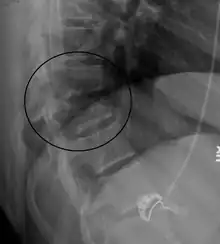

A flexion-distraction fracture of T10 and fracture of T9 due to a seatbelt during an MVC.

On plain X-ray, a Chance fracture may be suspected if two spinous processes are excessively far apart.[10]